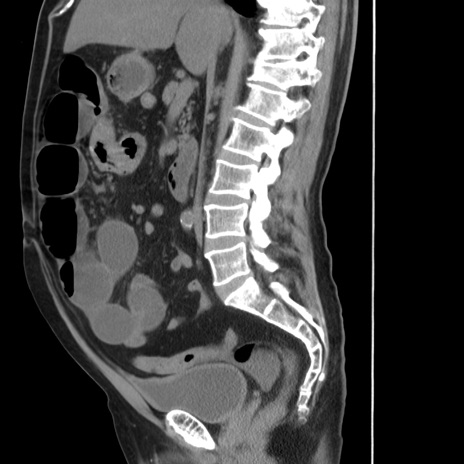

症例20(矢状断像)

【症例】 60歳代男性

【主訴】 腹部膨満、嘔吐

【現病歴】5日前頃より倦怠感を認め食事量減少し4日前の朝嘔吐、食事摂取困難となった。 3日前近医受診し点滴施行され整腸剤などを処方された。 当日他院を受診し、腹部膨満著明、炎症反応の上昇(CRP10.8、WBC11200)あり、紹介受診となる。

【身体所見】 意識JCS1 受け答えがはっきりしないBP 111/57mHg、 P 67bpm、、BT35.2°C、SpO2 97%(RA)、 腹部:膨隆、打診で鼓音あり、全体的に圧痛有り、腸蠕動音(-)、反跳痛ははっきりせず。

【データ】WBC 11400、CRP 14.20